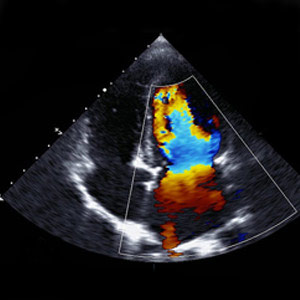

USG / ECHO Color Doppler

USG/ECHO color doppler is a medical ultrasonography that uses the doppler effect to take images of blood flow and tissues. The speed and direction can be visualized and determined by measuring the frequency shift of a specific sample volume, e.g., blood flow over a heart valve or flow in an artery. Color doppler determines the direction of blood flow in red or blue (either away or towards the transducer). Color doppler eco-cardiography is the primary method and consists of three components: proximal flow, proximal iso velocity surface area, and the vena contracta.